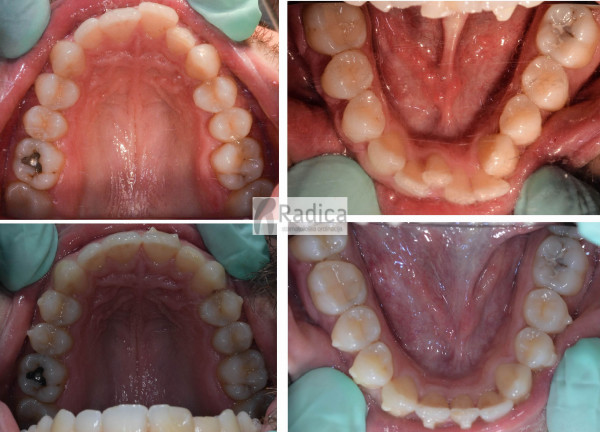

U galeriji slika su prikazani klinički slučajevi ovakvih odraslih pacijenta bilo da se radi samo o ortodontskoj terapiji ili predprotetskoj ortodonciji.

Kompresija –fiksni aparat bez ekstrakcije zuba

Slučaj 1

Slučaj 2

Slučaj 3

Slučaj 4